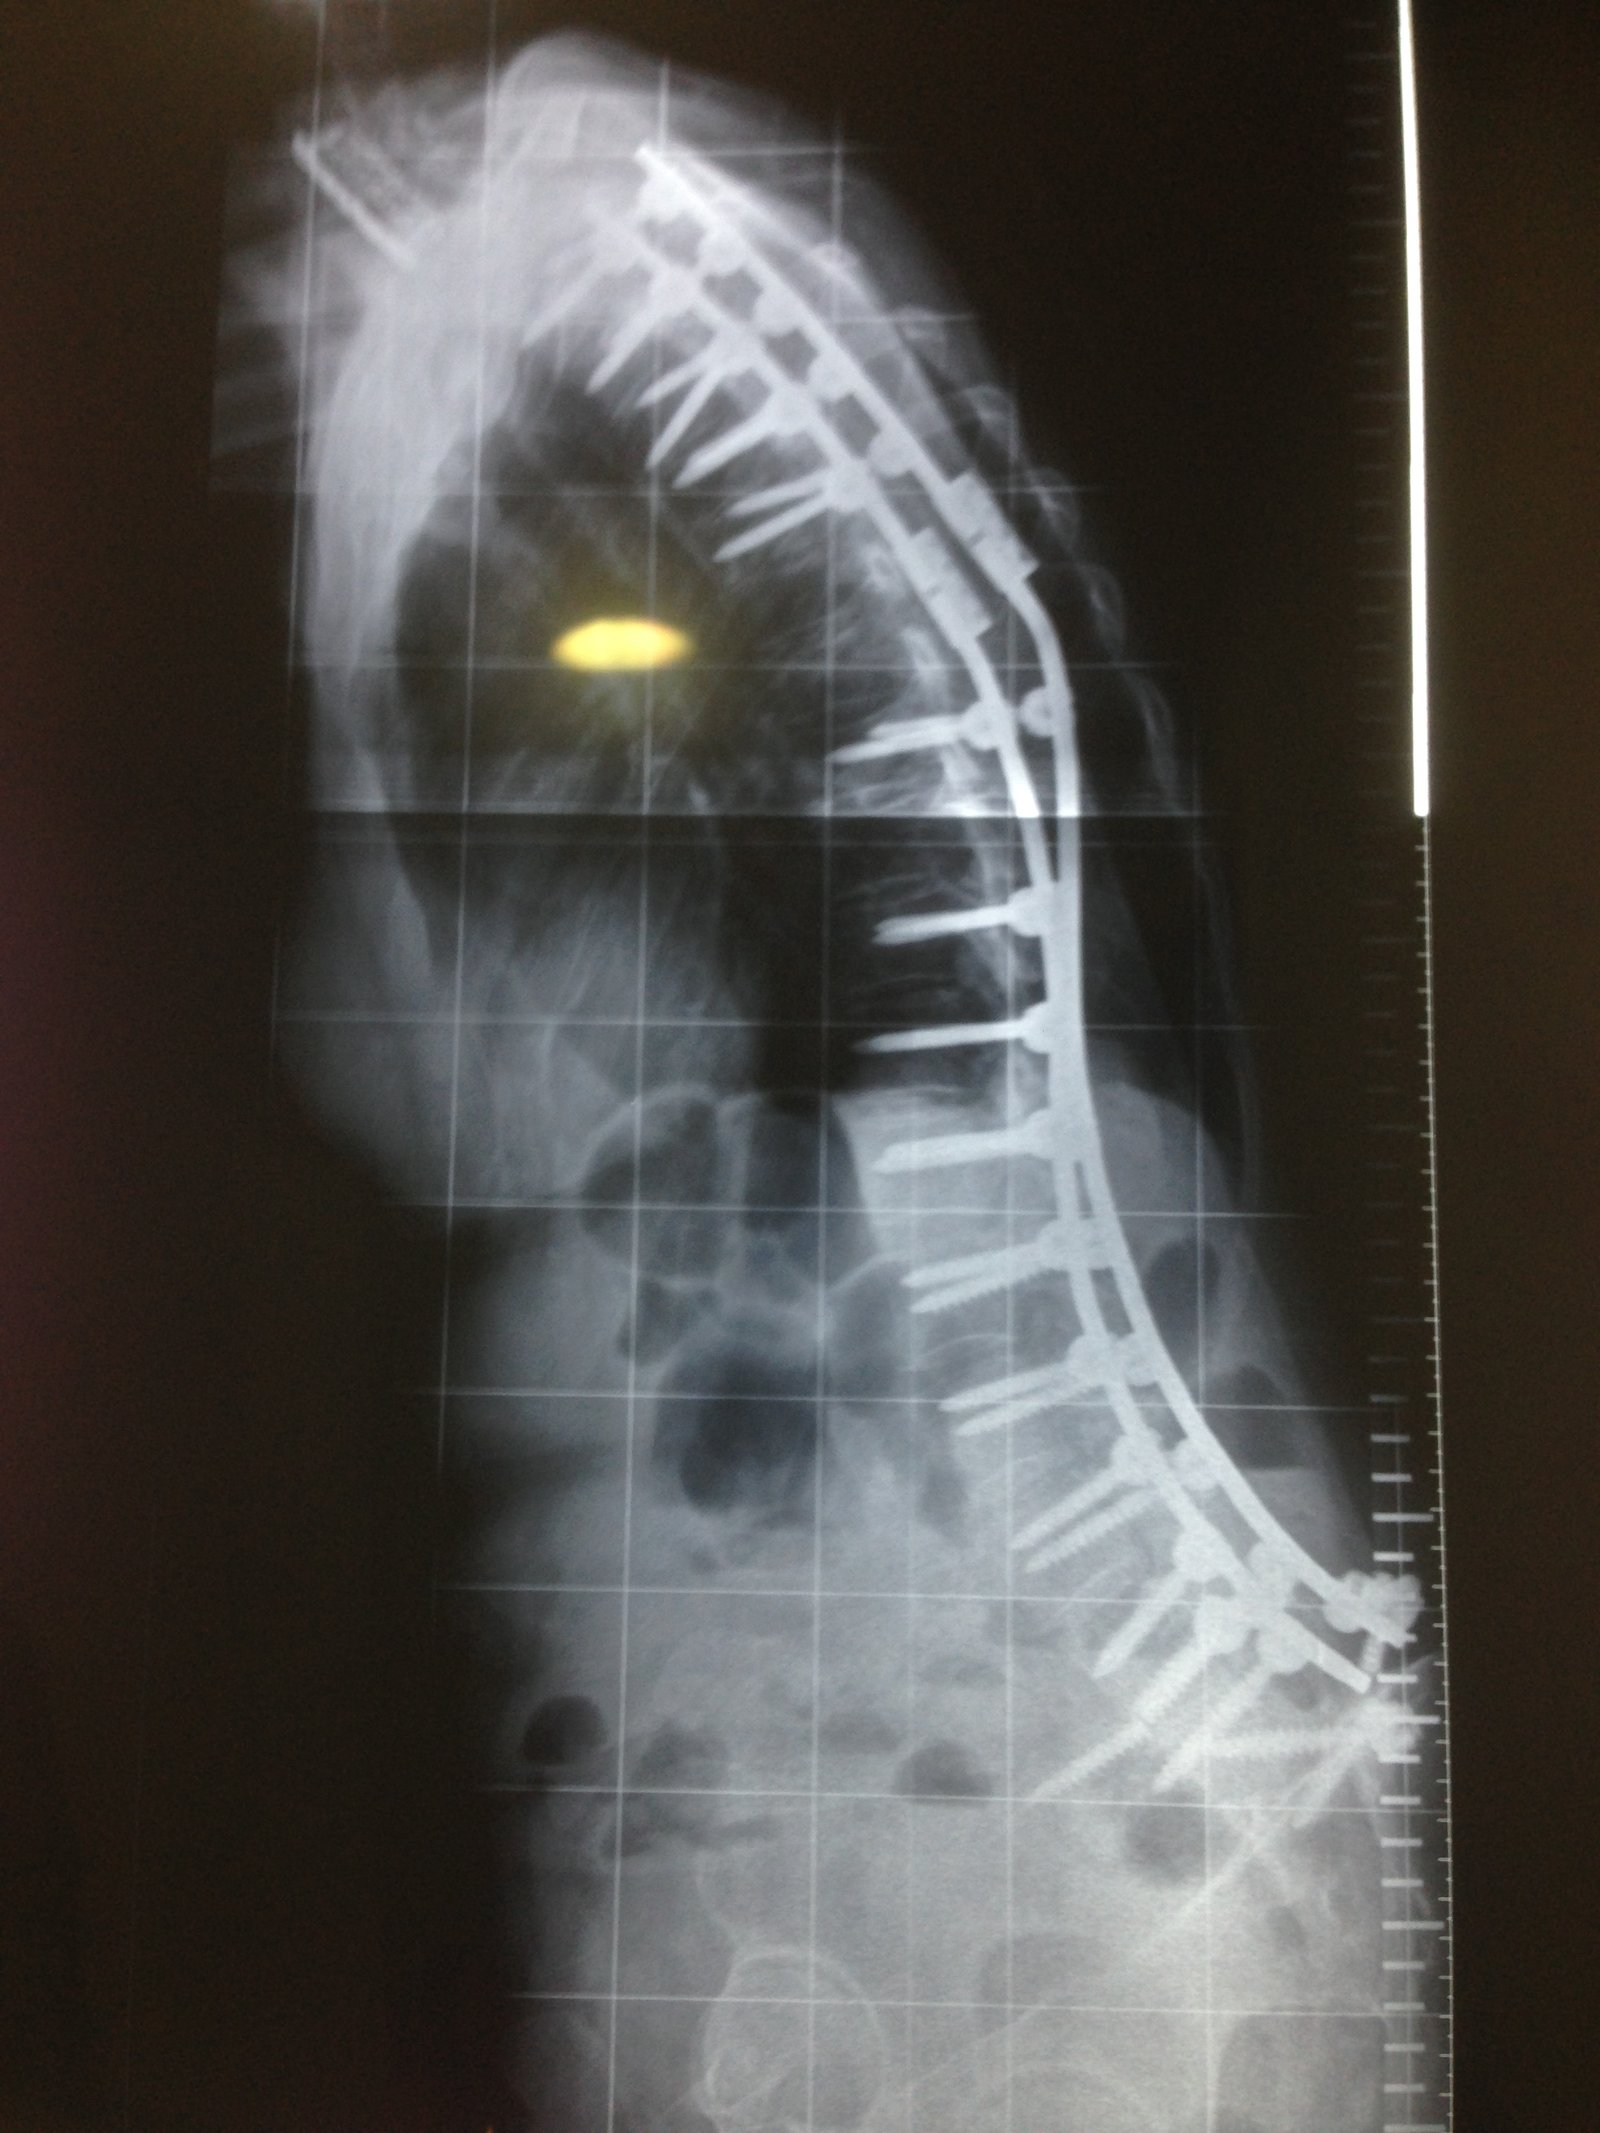

Estimulador de Cordones (SCS)

Tecnología que calma el dolor de forma automática, sin necesidad de cirugía mayor.